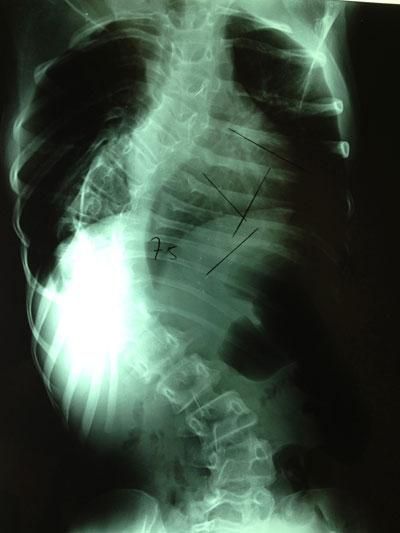

Διάγνωση της σκολίωσης

Πόσο φαίνεται η σκολίωσή μου;